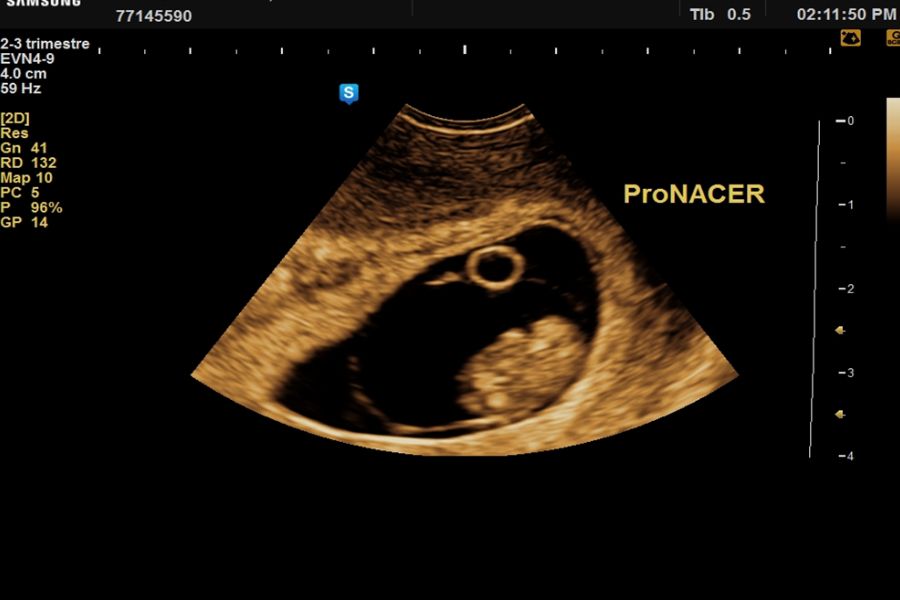

Ecografía de viabilidad desde las 6 a 10 semanas